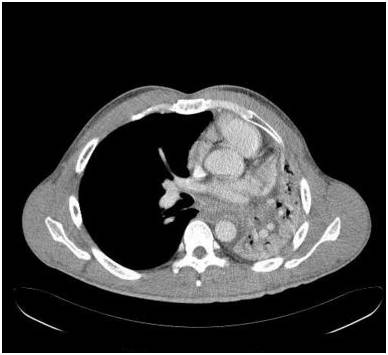

胸部前后位示弥漫不均匀的异常密度影,左肺体积缩小,左肺门区肿块样影与心膈角呈钝角。未增强纵隔窗CT示左肺肺不张,左主支气管完全受阻。增强CT示左主支气管及其段支气管内非强化的肿块。最小密度投影示左肺叶远端支气管重度狭窄,左主支气管及以下层面受阻。